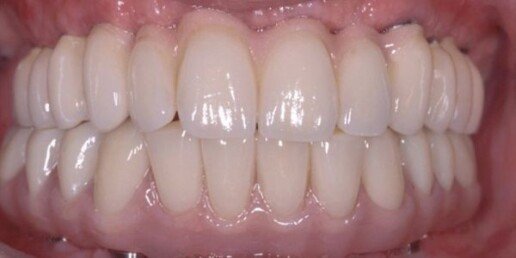

Caso 4

Riabilitazione totale superiore e inferiore su impianti. Gli esiti di una paradontite grave portano alla perdita totale dei denti. E’ necessario ricostruire sia i denti sia i tessuti molli e anche l’osso per il sostegno delle labbra.

Prima

Dopo